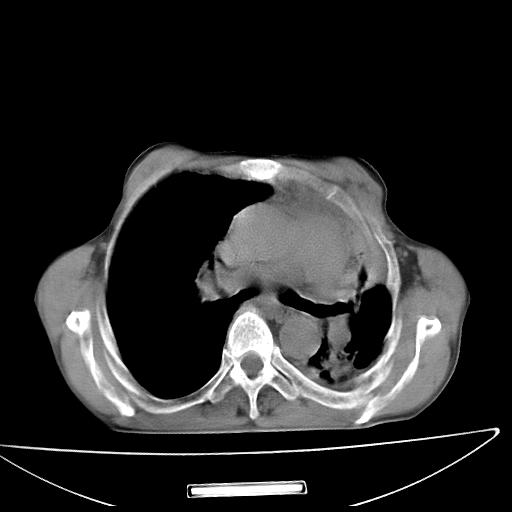

男  70岁,发烧咳嗽4天。盗汗,消瘦。无痰中带血丝,以前有肺tb病史,ct见,双肺tb,左侧胸廓塌陷,左胸膜肥厚粘连。纵隔移位,右侧胸腔积液,大家说说那个心影前左肺舌叶除了肺大炮还有炎症还是干酪性肺炎?有占位吗?我看纵隔淋巴结也大。

双肺继发性肺结核伴部分左肺毁损!

1)两肺继发性肺结核并左肺上叶肺不张,支气管扩张。2)双侧胸膜炎(胸膜增厚+少量胸腔积液)。

两肺继发性肺结核并感染,左肺上叶肺不张。建议ct增强。